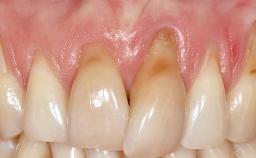

This case demonstrates that a connective-tissue graft in combination with a coronally positioned graft is an effective method of treating cases with peri-implant mucositis and an abutment-level sinus abscess. A 42-year-old man presented with a swelling adjacent to an implant crown at site 21. The swelling had been present for approximately three weeks and was constrained to the buccal and palatal gingival aspects of the implant. A discharge was noted on finger pressure, with localized gingival recession present on the mid- and distolabial aspects of the crown.